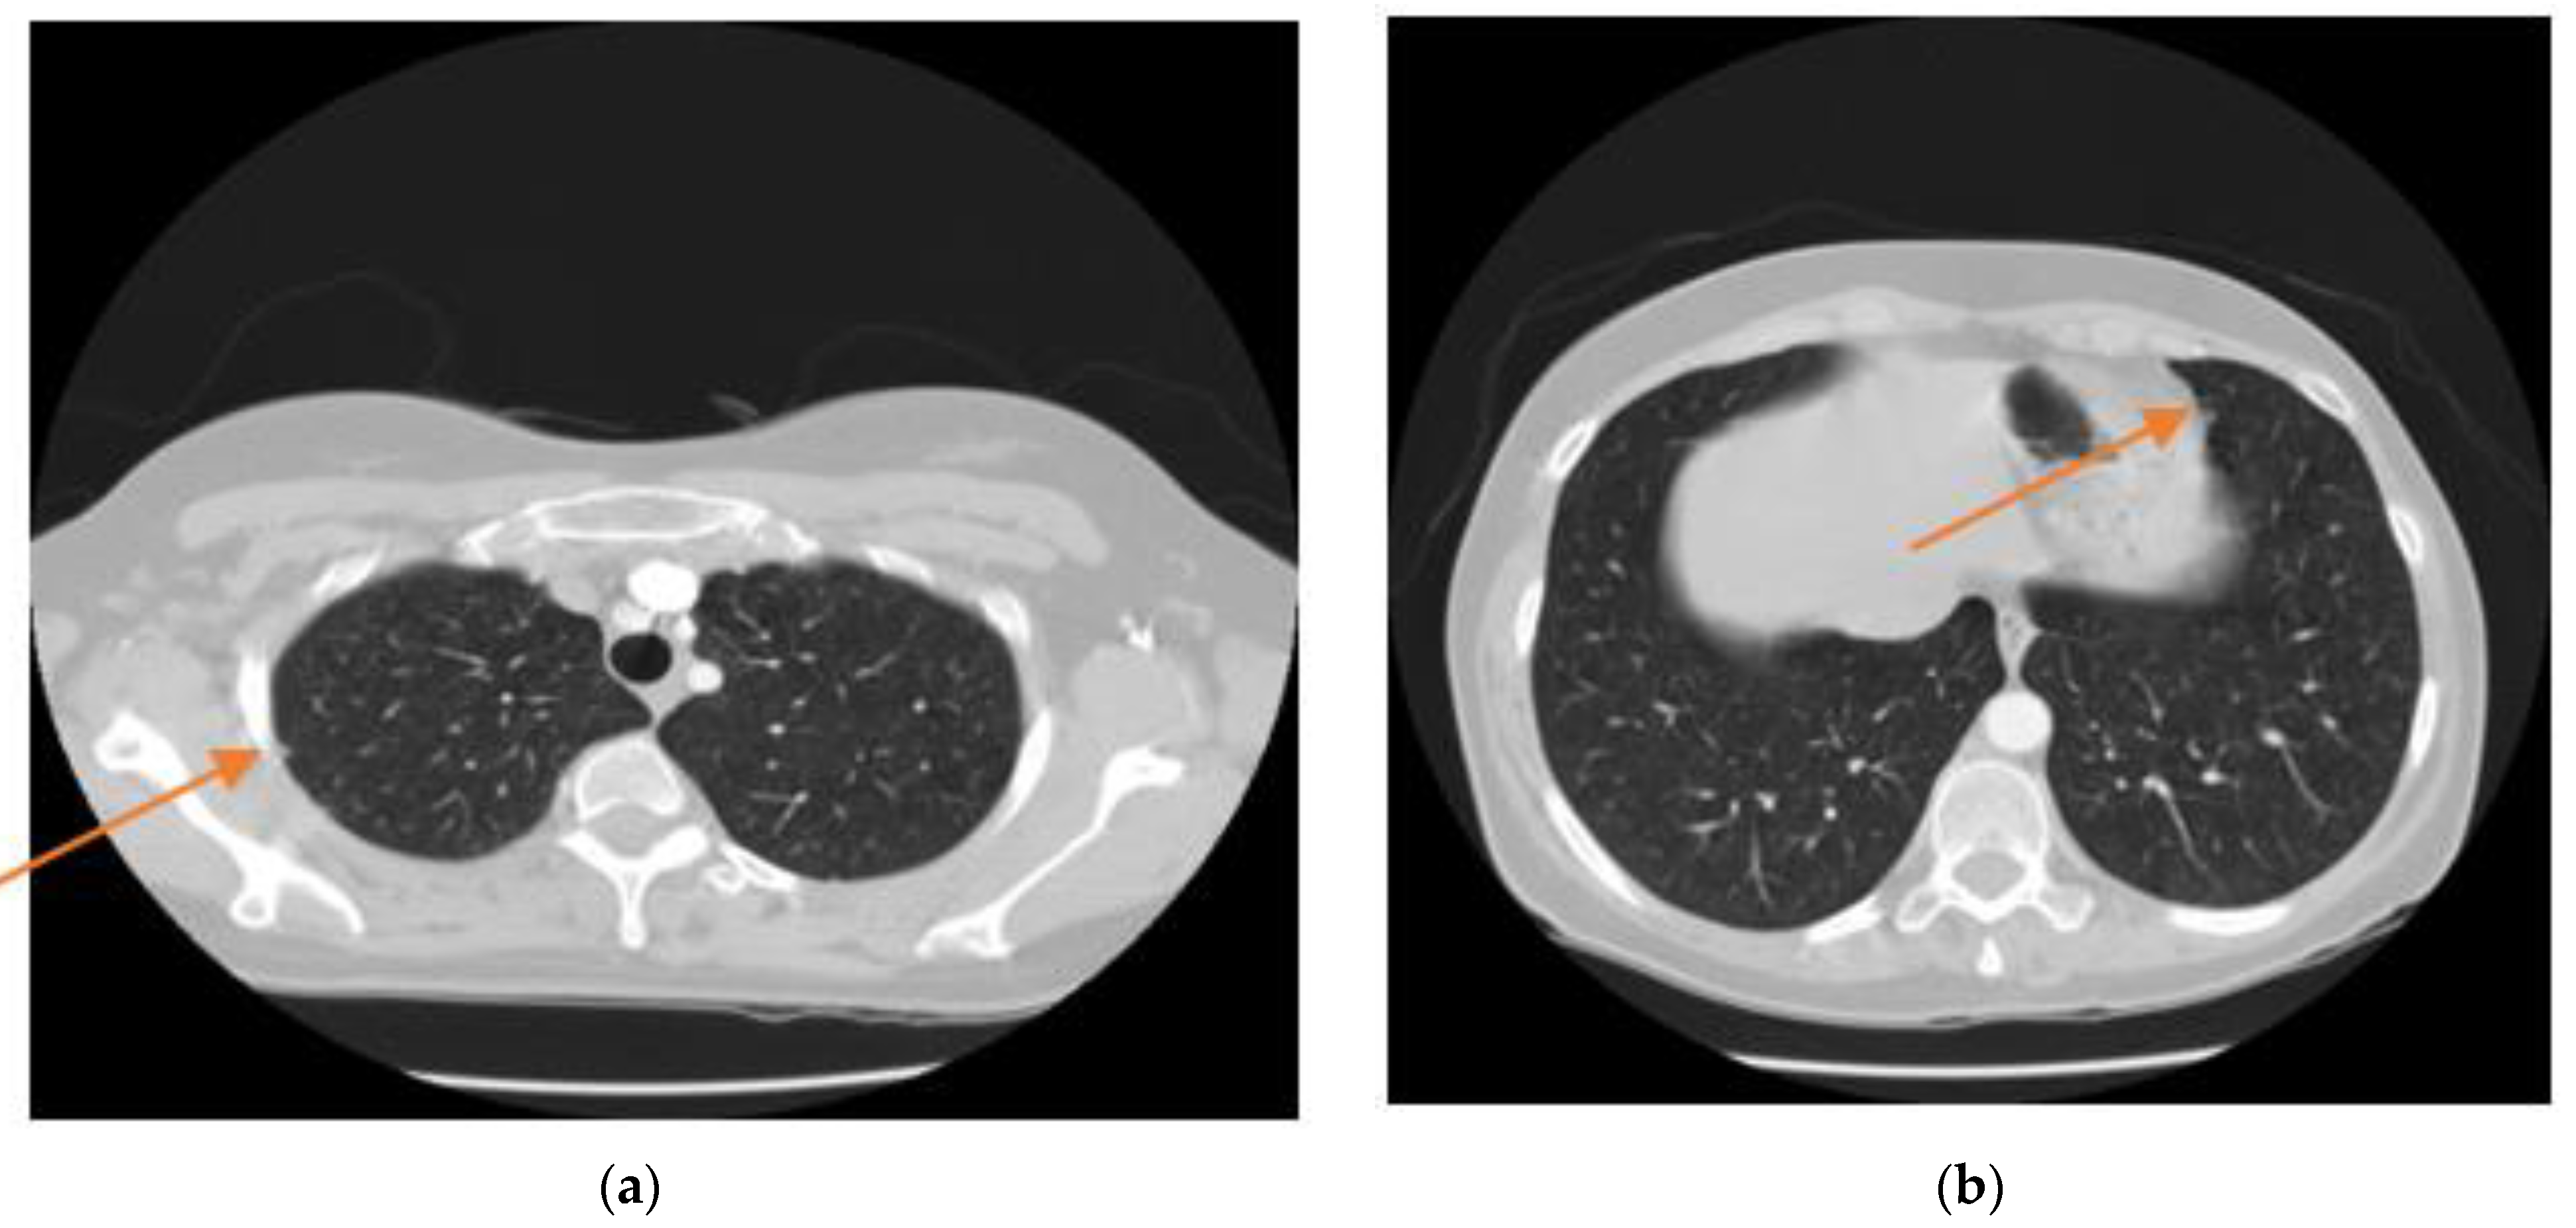

- Dilation morphological operation: Morphological operations, typically applied to binary images, are used to extract and describe the geometry of the object in the image [49,50]. As a result of the binarization process described before, there would still be remaining regions of white colour around the lungs regarded as unwanted noise. Thus, morphological operations can be used to remove these regions. Moreover, there could still be some small black holes in the lung’s region, suspicious of noise caused by the binarization process. These holes should be also removed using morphological operations.